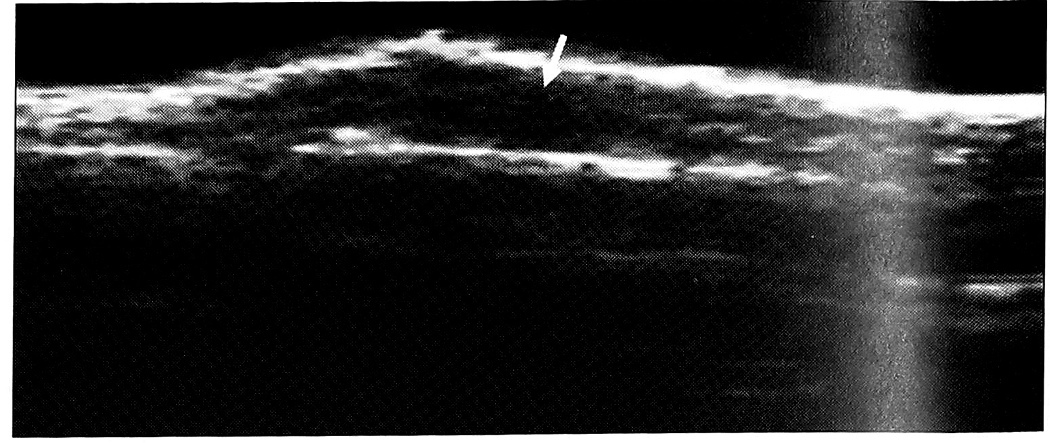

При расхождении концов сухожилия оно не визуализировалось в обычном анатомическом месте расположения. Концы сухожилия обнаруживались дистальнее и проксимальнее места повреждения (рис. 2). Диаметр проксимального конца в ряде случаев был увеличен вследствие его «захлеста». Если разрыву сухожилия не предшествовал патологический процесс, его эхографическая структура не изменялась. Между концами поврежденного сухожилия появлялась зона пониженной эхогенности, определялись озерцеподобные дефекты — участки неправильной формы, с неровными контурами, утратой структуры и почти полным отсутствием эхосигналов, соответствующие расположению гематомы. Следом за ними выявлялся эффект «засветления». Внутри этих участков иногда определялись движущие частички, дающие эхосигналы.

Рис. 2. Продольная сонограмма поврежденного сухожилия длинного сгибателя I пальца (10-й день после травмы). Дистальный конец сухожилия располагается на уровне межфалангового сустава, проксимальный — в области пястно-фалангового сустава (стрелка)